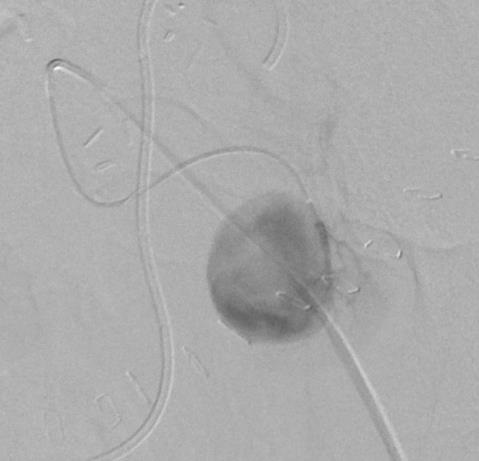

末端动脉栓塞:医源性肾损伤-移植肾活检

活检后动脉瘤破裂 |

微导管在载瘤动脉末端 |

载瘤动脉末端栓塞 |

Coil=3 |